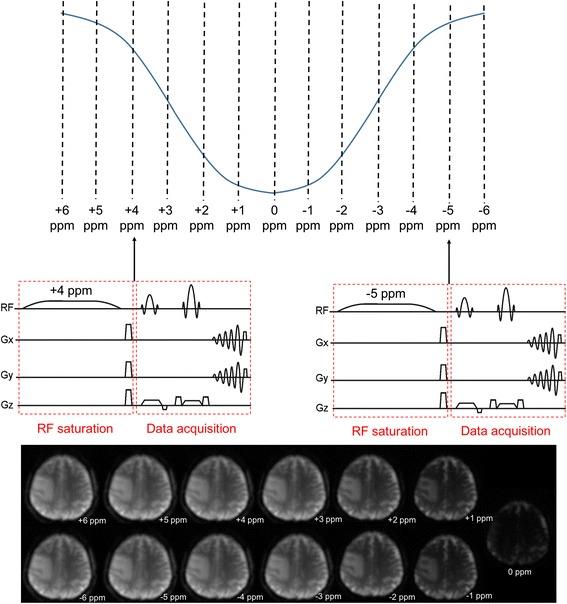

The search for novel image contrasts has been a major driving force in the magnetic resonance (MR) research community, in order to gain further information on the body's physiological and pathological conditions.Chemical exchange saturation transfer (CEST) is a novel MR technique that enables imaging certain compounds at concentrations that are too low to impact the contrast of standard MR imaging and too low to directly be detected in MRS at typical water imaging resolution. For this to be possible, the target compound must be capable of exchanging protons with the surrounding water molecules. This property can be exploited to cause a continuous buildup of magnetic saturation of water, leading to greatly enhanced sensitivity.The goal of the present review is to introduce the basic principles of CEST imaging to the general molecular imaging community. Special focus has been given to the comparison of state-of-the-art CEST methods reported in the literature with their positron emission tomography (PET) counterparts.